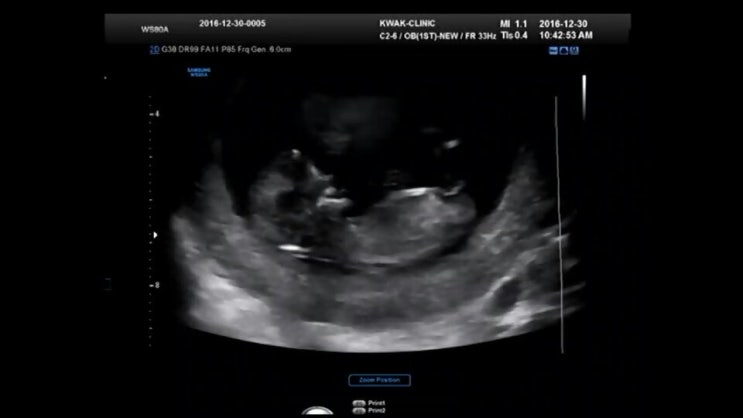

[임신 6주] 신혼 3년 차, 비단이를 만나다

16년도에는 내게 유독 많은 일들이 있었다. 직장을 그만두었고, 3개월 휴식 끝에 다니던 회사를 다시 복직...